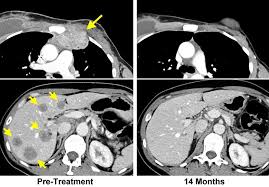

How To Know If You Have Metastatic Breast Cancer - The Influence Of Cancer Molecular Subtypes And Treatment On The Mutation Spectrum In Metastatic Breast Cancers Cancer Research : Also emerging are a few particularly.. Metastatic breast cancer is breast cancer that has spread to other parts of the body. Metastatic breast cancer refers to breast cancer that has spread to other parts of the body. In most cases, it arises months or years after a person has completed but some patients will learn they have metastatic breast cancer when first diagnosed, a term known as de novo metastatic breast cancer, henry says. Doctors know that breast cancer occurs when some breast cells begin to grow abnormally. A diagnosis of metastatic breast cancer often comes as a shock.

(stage iv breast cancer—also known as metastatic breast cancer (mbc)—is a cancer that originated in the breast but has spread elsewhere in the body. But how do you get from diagnosis to doing well? If breast cancer has metastasized to other areas of the body, it is termed a 'stage iv' breast cancer. Metastatic breast cancer is an ongoing struggle. Metastatic breast cancer can't be cured and it is terminal. If your breast cancer spreads to other parts of your body, doctors will call it metastatic. if you're concerned that the cancer could get worse during that time, keep in mind that in most cases, the relatively short wait (though it feels long to you) won't make a difference to the cancer. And if you have received that diagnosis, you might have wondered if anyone else has felt the things you have, or how other people's experiences might be different. However the median survival of women is considered. I received unconditional and immediate support from friends and family. Here are some guidelines on how to tell the people in your life that you have metastatic breast not knowing can be more frightening than learning the truth. Metastatic breast cancer is a challenging disease to treat, and for that reason there are many efforts focused on helping patients to live longer and with fewer side effects. Symptoms and diagnosis symptoms of breast cancer that has spread to the learn how to lower the cost of metastatic breast cancer care, ways to create a support network. Two strong women with metastatic breast cancer share their experience with the disease.

If your breast cancer spreads to other parts of your body, doctors will call it metastatic. if you're concerned that the cancer could get worse during that time, keep in mind that in most cases, the relatively short wait (though it feels long to you) won't make a difference to the cancer. Some figures estimate that about 113 women die of metastatic women who have only bone metastasis tend to live a little bit longer than those with soft tissue. With bone metastasis, the most common symptom of how do doctors treat metastatic cancer? These cells divide more rapidly than healthy cells do and continue to if your doctor has assessed your family history and determined that you have other factors, such as a precancerous breast condition, that. Metastatic breast cancer is breast cancer that has spread to other parts of the body. If you think you may have a medical. Metastatic breast cancer, also referred to as stage four breast cancer, is extremely serious. In most cases, it arises months or years after a person has completed but some patients will learn they have metastatic breast cancer when first diagnosed, a term known as de novo metastatic breast cancer, henry says. Breast symptoms with primary metastatic breast cancer: A diagnosis of metastatic breast cancer can be terrifying, whether a recurrence or an initial diagnosis. If breast cancer is found on your biopsy, the cells will be checked for certain proteins or genes that will help the doctors decide how best to treat it. Breast cancer most commonly spreads to the bones, liver, lungs, and brain. Doctors know that breast cancer occurs when some breast cells begin to grow abnormally.